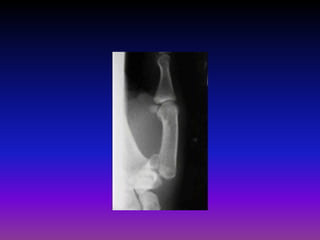

Dinner fork Deformity

Colles’ Fracture

• Transverse fracture at the

Displacements